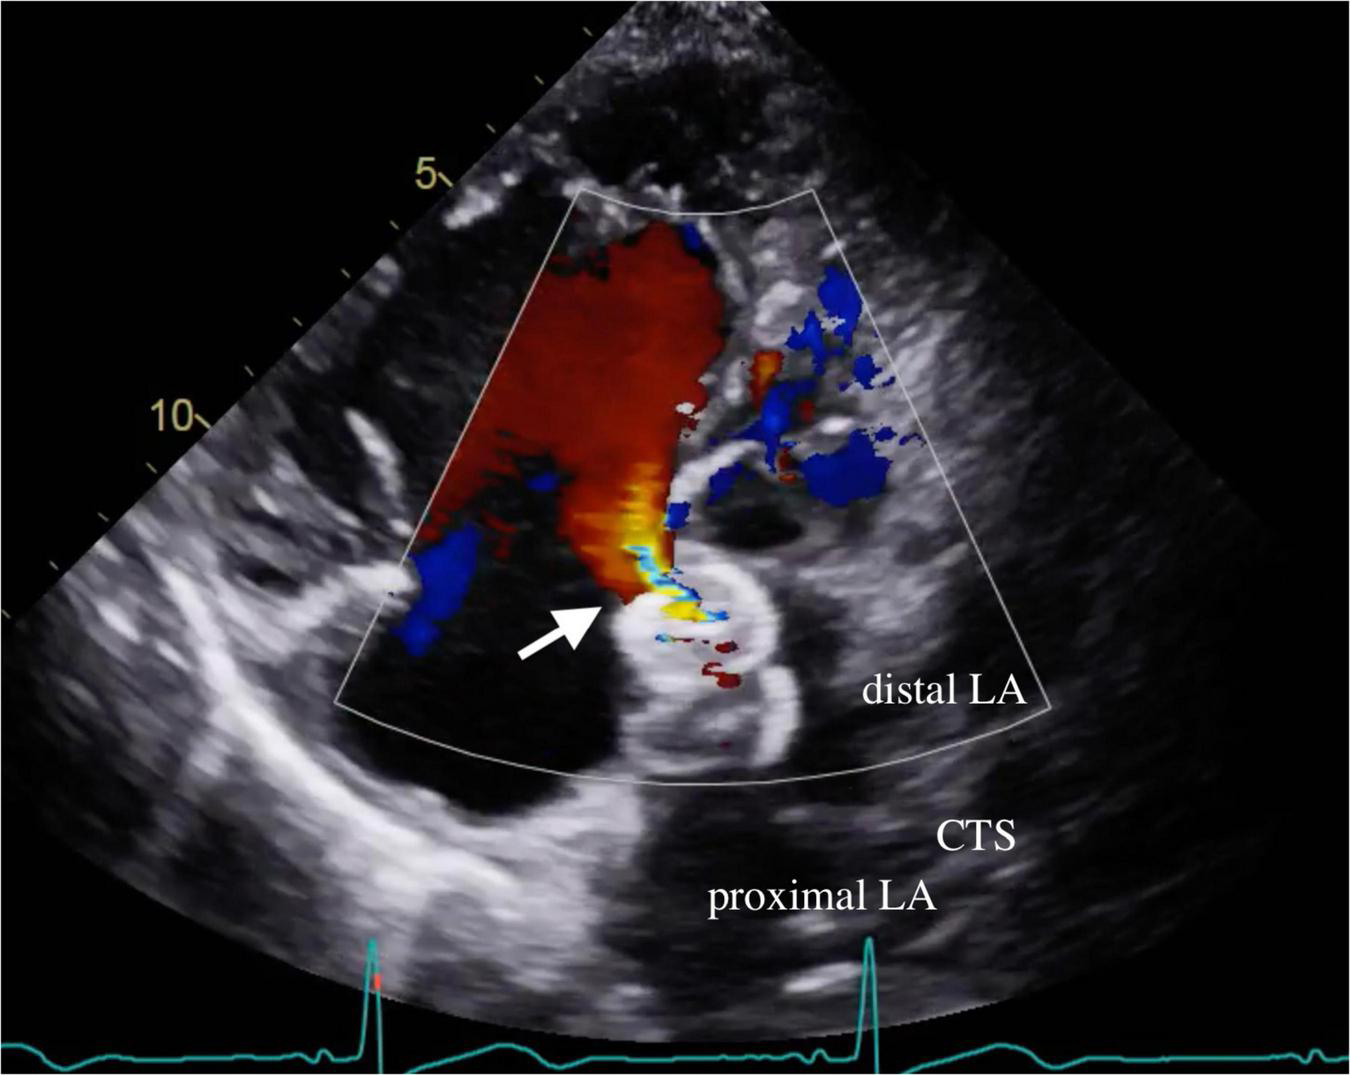

FIGURE 2

Residual ASD shunt. Transthoracic echocardiography demonstrated residual shunting (arrow) through the waist of the ASD device. ASD denotes atrial septal defect; CTS denotes cor triatriatum sinister; LA denotes left atrium.